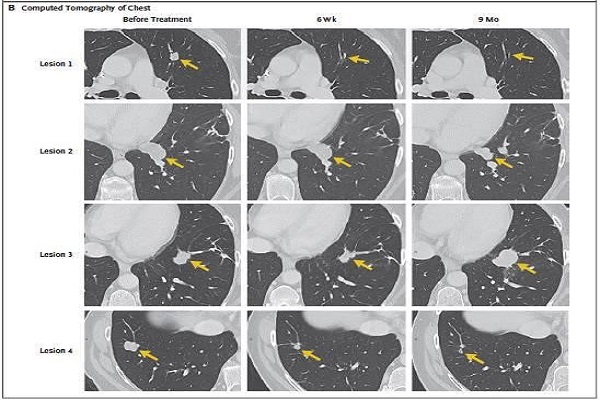

TIL 기반의 치료법은 다양한 고형 종양에서 이용할 수 있으며, 현재 Iovance는 흑색 종에 대한 LN-144와 다른 고형 종양에 대한 LN-145를 개발하여 임상 진행 중에 있습니다. 진행중인 임상 시험에는 흑색 종, 난소 암, 자궁 경부암, 두경부 편평 세포 암종 및 비소 세포 폐암이 포함됩니다.

![]() [자궁 경부암 전이 후 치료사례] |